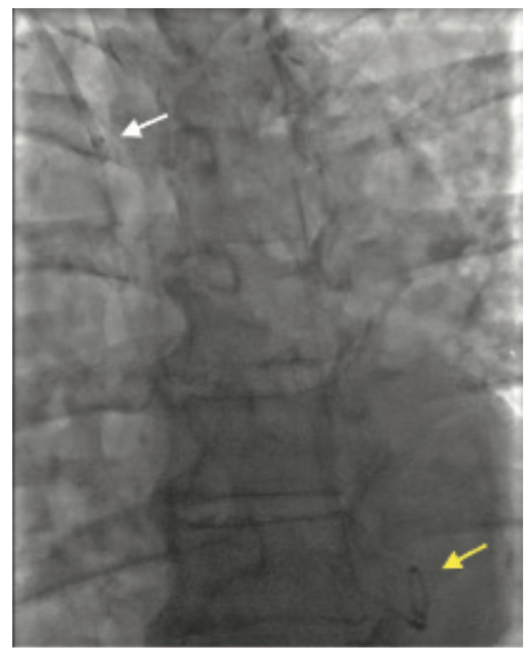

An 82-year-old female presented with New York Heart Association (NYHA) Class III dyspnea and Canadian Cardiovascular Society (CCS) Class III angina. Other comorbidities include severe cardiomyopathy with reduced ejection fraction (EF) of 25%-30%, severe functional mitral regurgitation, chronic kidney disease stage III, and severe frailty. A diagnostic coronary angiogram revealed severe multivessel disease involving the right coronary artery (RCA) and left anterior descending (LAD) artery. More importantly, the patient had a tortuous brachiocephalic artery with a 360-degree loop (Figure 1). She was evaluated by a heart team and found to be at high risk for surgery with a Society of Thoracic Surgeons (STS) score of >8%. A decision was made to perform percutaneous coronary intervention (PCI) followed by percutaneous valve repair in a staged fashion.

Access site selection was paramount in our frail, elderly female to reduce vascular complications. Despite radial access being our preferred first access, there were some concerns, given a severely tortuous brachycephalic artery. The ascending aorta was accessed with a stiff angled Glidewire (Terumo) followed by an Amplatz Super Stiff™ guidewire (Boston Scientific) in an effort to straighten the brachiocephalic loop, but with no success. We accessed the ascending aorta with a 6 French (F) 75 cm R2P™ DESTINATION SLENDER™ Guiding Sheath. Image-guided RCA PCI was completed uneventfully, despite the presence of a 360-degree right brachiocephalic loop (Figure 1A-D).